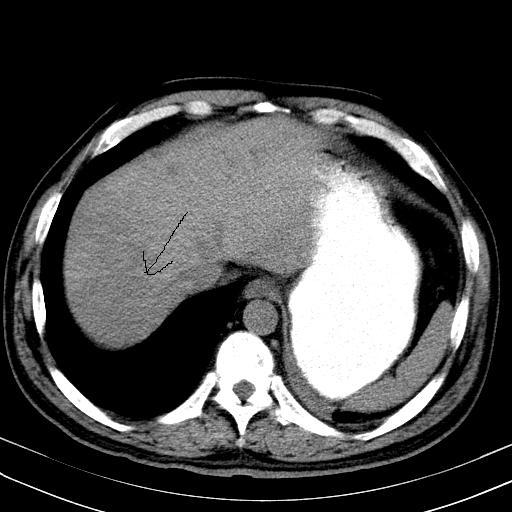

先行ct平扫,纵膈内多发软组织影,ct值约为36hu,以下为增强扫描和腹部平扫。

大家看看肝脏右叶片状低密度影是什么改变啊?

淋巴瘤?肝脏请增强后说啊

多发肿大淋巴结影,肝内改变需结合强化观察

多发肿大淋巴结影,肝内改变需结合强化观察。